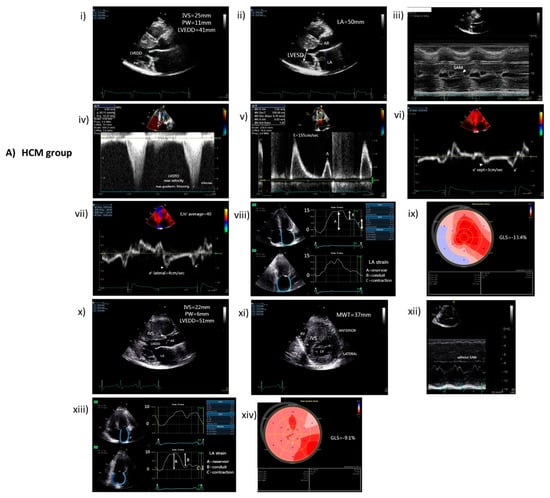

| HCM (n = 46) | Non-HCM (n = 27) | Significance (p-Value) | |

|---|---|---|---|

| LVEDD (mm) | 47 (±7) | 47 (±4) | 0.893 |

| LVESD (mm) | 30 (±6) | 31 (±4) | 0.684 |

| IVS (mm) | 18 (±4) | 10 (±2) | <0.001 |

| PW (mm) | 11 (±2) | 9 (±1) | 0.005 |

| MWT (mm) | 19 (±3) | 10 (±2) | <0.001 |

| LV mass index (g/m2) | 137 (±30) | 77 (±23) | <0.001 |

| Location of asymmetric LV hypertrophy | |||

| IVS | 39 (84%) | - | |

| Apex | 4 (9%) | - | |

| Mixed | 3 (7%) | - | |

| LVOTO (mmHg) | 14 (30%) 61 mmHg ± 35 | - | |

| LVEF (%) | 58 (±8) | 60 (±4) | 0.435 |

| GLS (%) | −14 (±6) | −20 (±2) | <0.001 |

| LA diameter (mm) | 47 (±7) | 39 (±5) | <0.001 |

| LA volume index (mL/m2) | 51(±18) | 29 (±10) | <0.001 |

| E/e’ratio | 13 (±7) | 8 (±3) | <0.001 |

| LA strain (reservoir) | 20 (±7) | 31 (±9) | <0.001 |

| LA strain (conduit) | −10 (±5) | −15 (±5) | 0.001 |

| LA strain (contraction) | −10 (±5) | −16 (±6) | <0.001 |